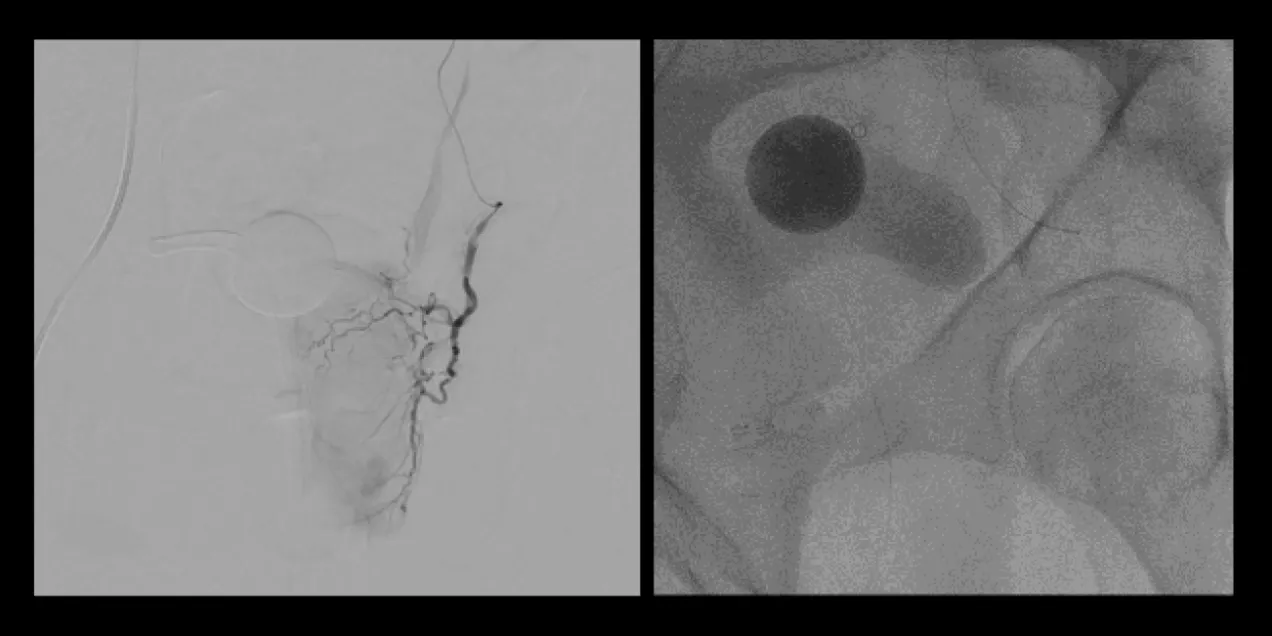

picture 2Overall, the procedure involves shrinking the prostate by treating its blood vessels. An interventional radiologist gains access through a small incision in the upper thigh or the wrist. From there, small particles are injected into the prostate to slow the blood flow to the gland, causing the prostate to shrink. Relief from BPH symptoms occurs in the following weeks and months. It is a relatively painless procedure using conscious sedation. After the procedure, UCSF Radiology follows up with patients at one, six and 12 months.